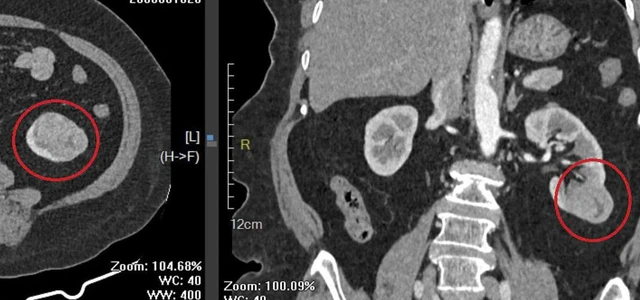

Trong quá trình thăm khám và thực hiện các xét nghiệm cận lâm sàng phục vụ phẫu thuật, các bác sĩ phát hiện khối u tại thận trái.

Hình ảnh khối u thận trái của người bệnh qua phim chụp cắt lớp vi tính. Ảnh: BVCC.